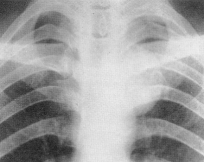

HERNIA PULMONARĂ MEDIASTINALĂ

Hernia se produce īn zonele cu rezistenta anatomica scazuta ; anterior, prin spatiul retrosternal, si posterior, īntre cord si aorta descendenta - mult mai rar.

Imaginea radiologica de fata evidentiaza o hipertransparenta, ovalara sau rotunda care depaseste umbra mediastinului, convexa lateral, bine delimitata de linia opaca realizata de cele patru foite pleurale si tesutul celular mediastinal care le reuneste.